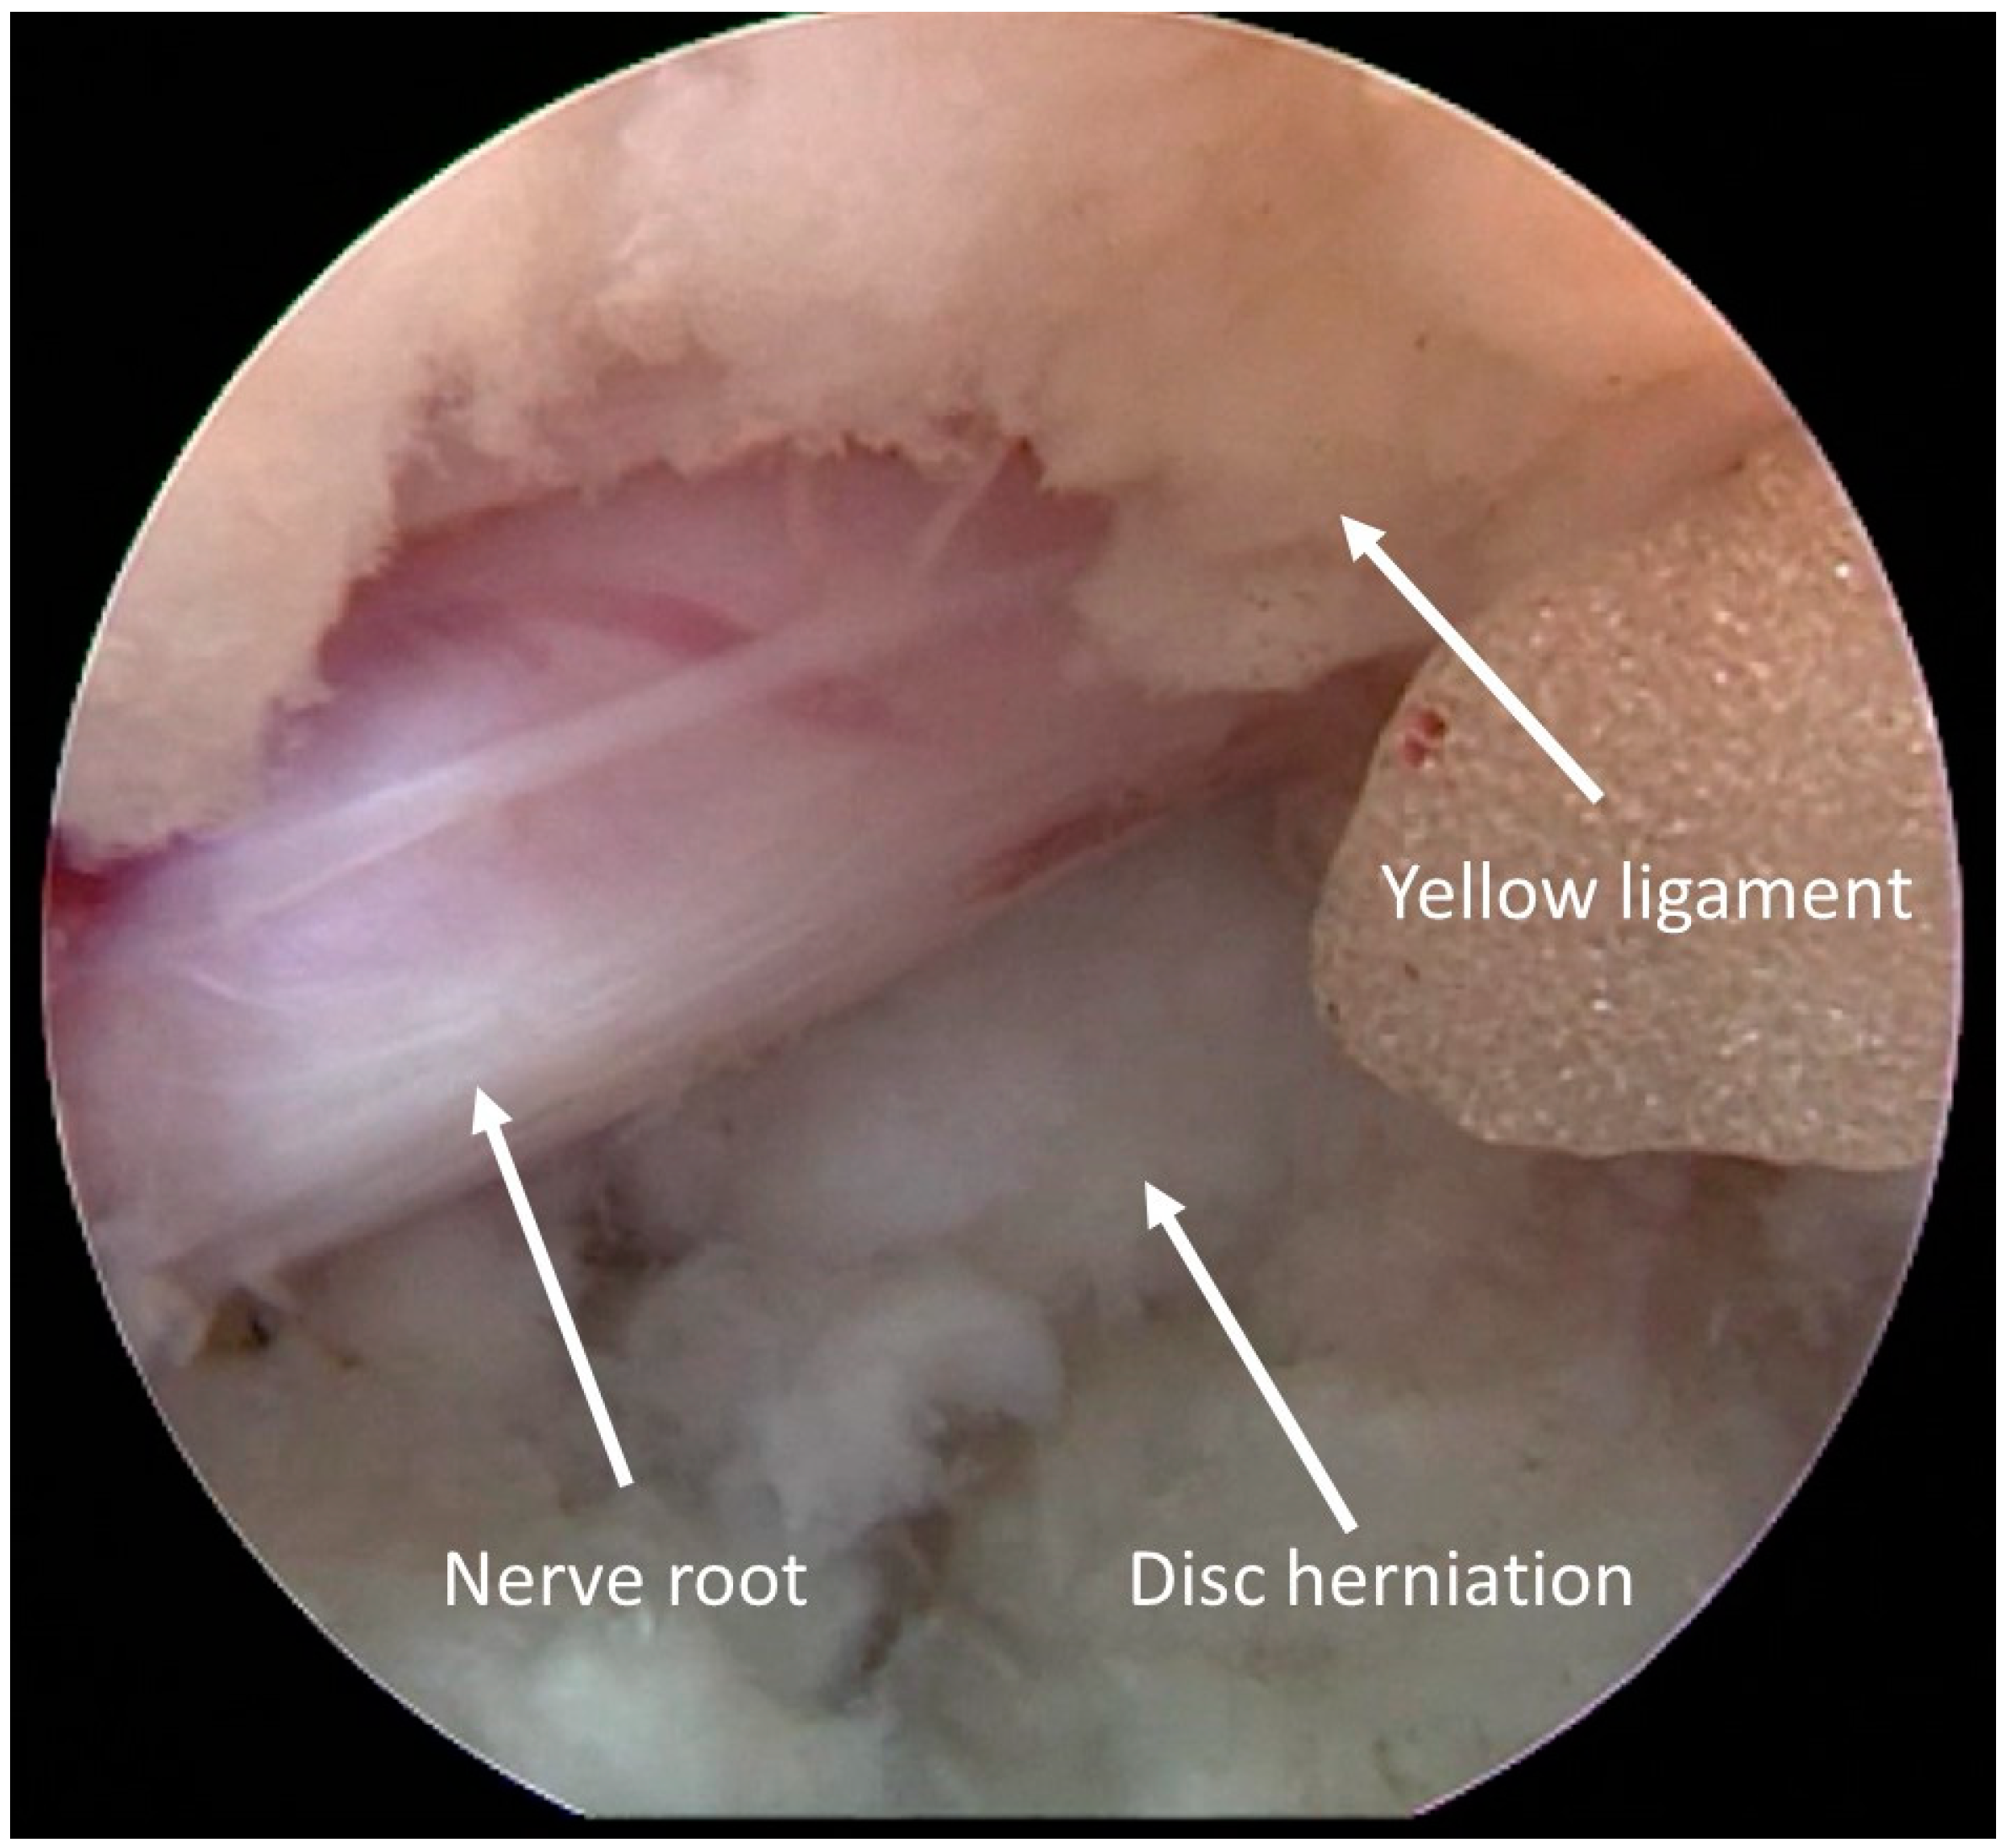

2. Materials and Methods

2.3. Surgical Data